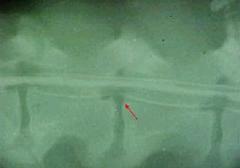

examen radiologic cu contrast pozitiv (cu substanta de contrast) al vezicii urinare

Radiografie cu contrast pozitiv

• Cerinte suplimentare – examen radiologic al coloanei vertebrale, mielografie

Diagnostic

compresiune medulara de la T13 pâna la L3 (se observa foarte bine cum discurile intervertebrale comprima maduva spinarii)

spondilartroza la L1 – L4 (depuneri de osteofite)